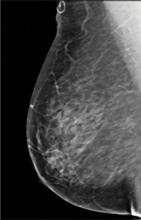

In addition to women with dense breasts, there are also other women for whom mammographic screening is not really enough, which is why research needs to continue in this field. Dr. Wendie Berg, a leading breast cancer specialist, talks with ITN about new research and advancements in breast imaging technology.

Dr. Berg, MD, PhD, FACR, FSBI, is Professor of Radiology at the University of Pittsburgh School of Medicine and Magee-Womens Hospital of UPMC, specializing in breast imaging. She is also the Chief Scientific Advisor to DenseBreast-info.org. A renowned expert, she writes and co-edits one of the leading textbooks on the topic, Diagnostic Imaging: Breast, currently in its third edition, and has co-authored over 120 peer-reviewed research publications.

It has long been said that a national reporting standard is needed in order to ensure all American women receive at least the same basic information regarding breast density, and a spotlight put on the importance of routine breast imaging. Dr. Wendie Berg, a leading breast cancer specialist, shares with ITN what is being done in the fight against breast cancer and the importance of this standardization in reporting for women.